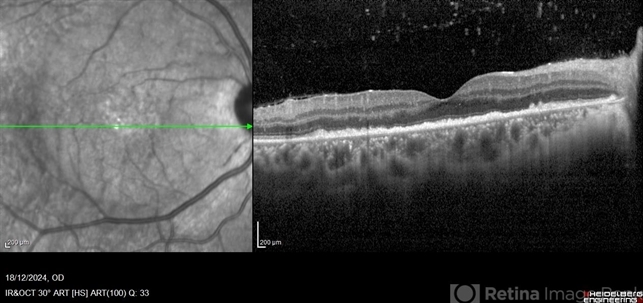

- Ocular syphilis, acute syphilitic posterior placoid chorioretinitis, OCT

Optical coherence tomography system

Heidelberg Spectralis - Description

- A 36-year-old male with bilateral visual loss of 3 months' duration, with no relevant medical history on inquiry. A round-shaped lesion with well-defined borders and a yellowish-white color is observed in the macula of both eyes, accompanied by vitreous cellularity. The macular OCT shows a dentate RPE. The VDRL, FTA-ABS, and HIV tests were positive.